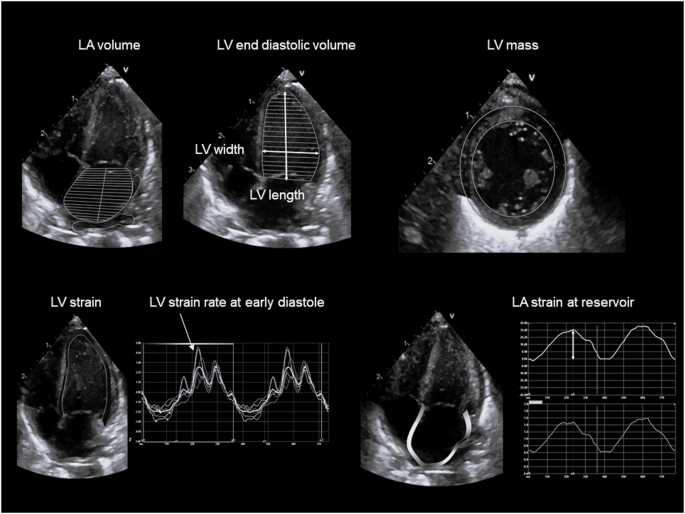

Images were acquired according to the recommendations of the American Society of Echocardiography and the targeted neonatal echocardiography recommendations and saved at 100 and 200 mm/s sweep speeds [8]. Ultrasound parameters of interest for multimodal LV diastolic function assessment are presented in Table 1, Figs. 1 and 2 and included cardiac size and shape, blood flow velocities, myocardial velocities and myocardial shortening. Most measurements were derived from a 3-beat average at 200 mm/s sweep speed. Partial fusion of the diastolic wave forms is common in preterm infants. When full fusion was apparent, we ensured the infant was settled using facilitated tucking and sucrose before further image acquisition was attempted. Doppler images with persistent full fusion between the early and late diastolic wave forms were omitted from analysis. Strain measurements were taken from apical 4-chamber images in adult orientation, from one heartbeat, and analysed by one investigator using a 6-segment (LV) or 3 segment (LA) model. Images were selected based on image quality criteria such as level of foreshortening, gain settings, clarity of borders, presence of artefacts, frame rate and tracking quality. Pulmonary vein Doppler was not part of our cardiac ultrasound protocol in this epoch.

Feasibility was good for most diastolic parameters to average for some: PW velocities 92%, PW timings 77%, TDI velocities 94%, TDI timings 97%, volumes 99%, LV strain 81%, LA strain 85%.